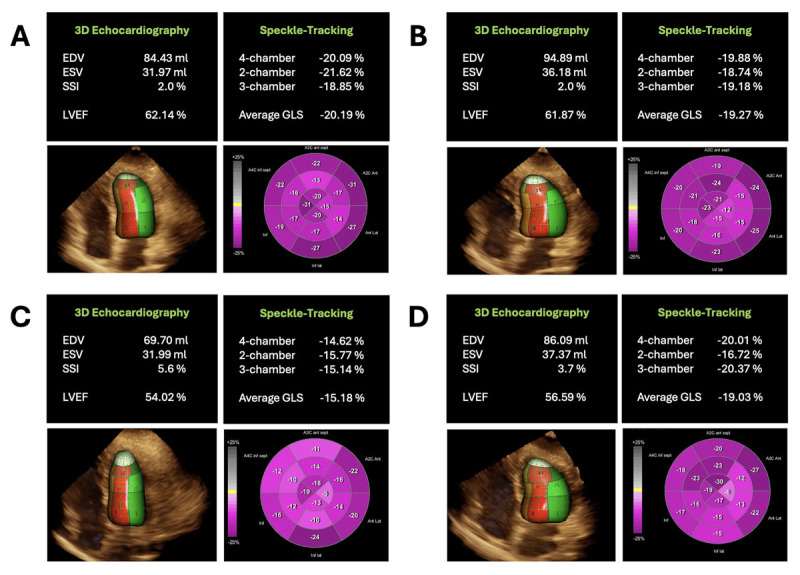

化疗明显改善了癌症的治疗效果,但与癌症治疗相关的心功能不全(CTRCD)仍是一项重大挑战,约有 10% 的患者会受到影响。CTRCD 可无症状或伴有心衰症状。多模态成像,尤其是超声心动图,仍然是监测心功能的关键。评估 CTRCD 的潜在生物标志物包括肌钙蛋白和 B 型钠尿肽。药物干预,如右雷佐生、血管紧张素转换酶抑制剂和他汀类药物,在初级预防和减轻心脏毒性以及心脏康复计划中发挥着至关重要的作用。因此,综合方法对于实现最佳心脏康复和改善患者预后至关重要。

Chemotherapy has markedly improved cancer outcomes, yet cancer therapy-related cardiac dysfunction (CTRCD) poses a significant challenge, affecting around 10% of patients. CTRCD can be asymptomatic or present with heart failure symptoms. Multimodality imaging, particularly echocardiography, remains pivotal for monitoring cardiac function. Potential biomarkers for CTRCD assessment include troponin and B-type natriuretic peptide. Pharmacological interventions, such as dexrazoxane, angiotensin-converting enzyme inhibitors, and statins, play a crucial role in primary prevention and mitigating cardiotoxicity alongside cardiac rehabilitation programs. Thus, a comprehensive approach is essential for optimal cardiac recovery and improved patient outcomes.